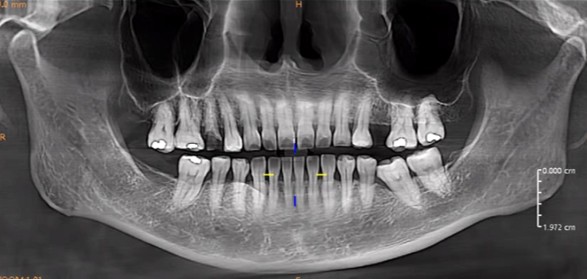

Panoramic radiograph shows inadequate obturation (radiolucent area) with white radiopaque material in the root canal of tooth 15